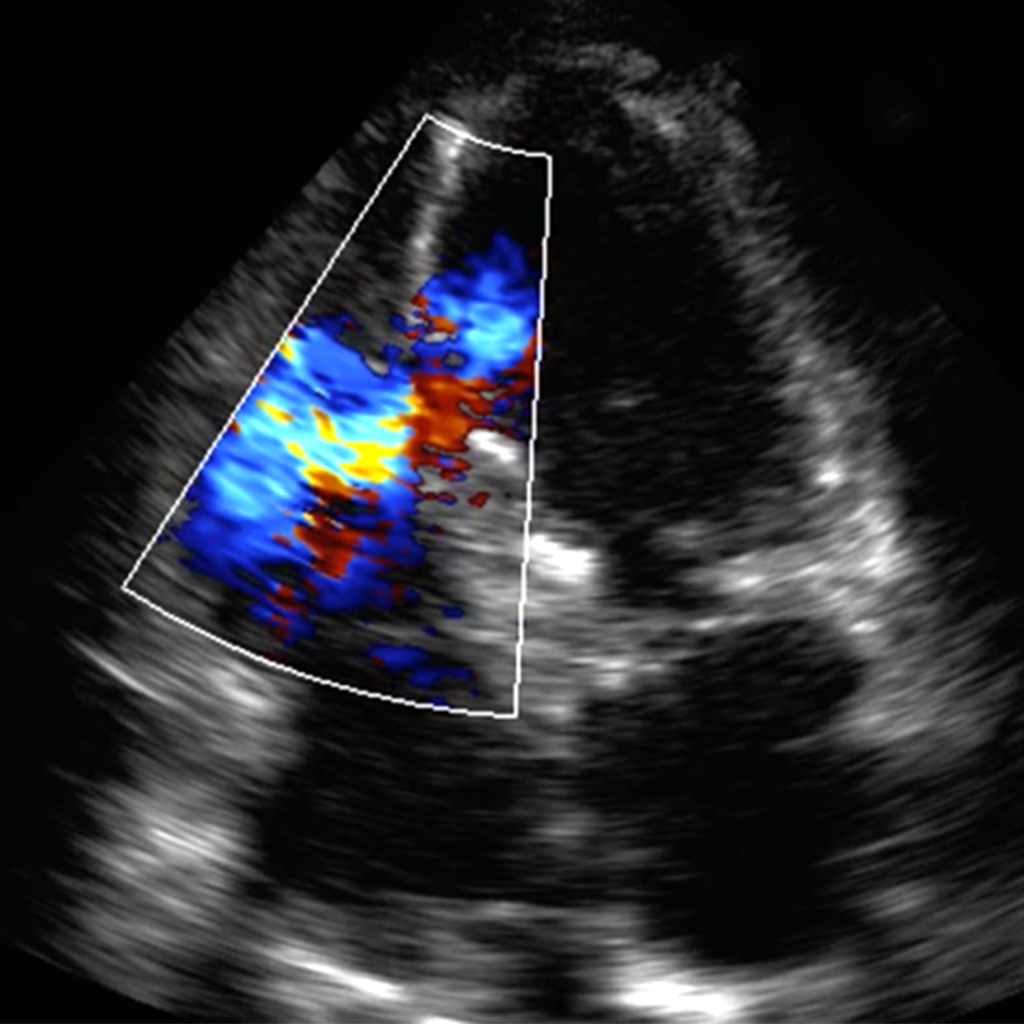

Focused Intensive Care Echocardiography (FICE)

Back to accreditation. Update, 2020 – FICE has now been merged with CUSIC creating…FUSIC. Minimal change to process for accreditation and FICE is now just incorporated

Point of care ultrasound (POCUS) is being increasingly utilised within acute and critical care environments as an adjunct to the clinical assessment of acutely unwell